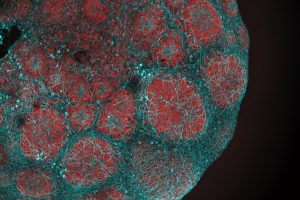

Angeborene Muskelschwäche: Muskeln können sich nicht regenerieren

Seit über 20 Jahren erforscht ein Team der Universität Basel eine schwere Form von Muskelschwäche, bei der die Muskeln allmählich absterben. Nun haben die Forschenden herausgefunden, dass auch die Regenerationsfähigkeit der Muskeln beeinträchtigt ist. Künftige Therapien sollten daher auch diesen As